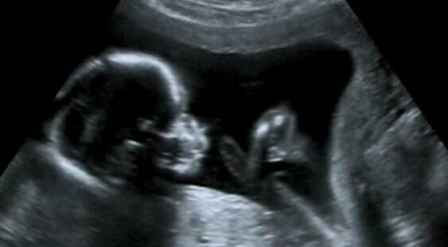

怀孕多久可以做b超 b超对胎儿有影响吗

04-28 阅读(0)怀孕是一生中非常重要的阶段,不仅关系到孕妇的健康,更重要的是影响到宝宝的健康。而B超则是怀孕期间必须做的检查,那么怀孕多久可以做b超?

b超对胎儿有影响吗

目前临床上所应用的B超,其探头发射的声强度小于10毫瓦/平方厘米,而且超声**的时间往往只有5~10分钟,对每个器官的探测时间更短.所以说,B超**对胎儿的危害是极小的,不会影响胎儿的身心发育.因此,孕妇不必对孕期B超**产生恐惧心理,适时的B超**是确保胎儿正常发育的重要手段.

正常情况下,妊娠早期应进行一次B超**,以明确是否妊娠,并确定妊娠的天数.